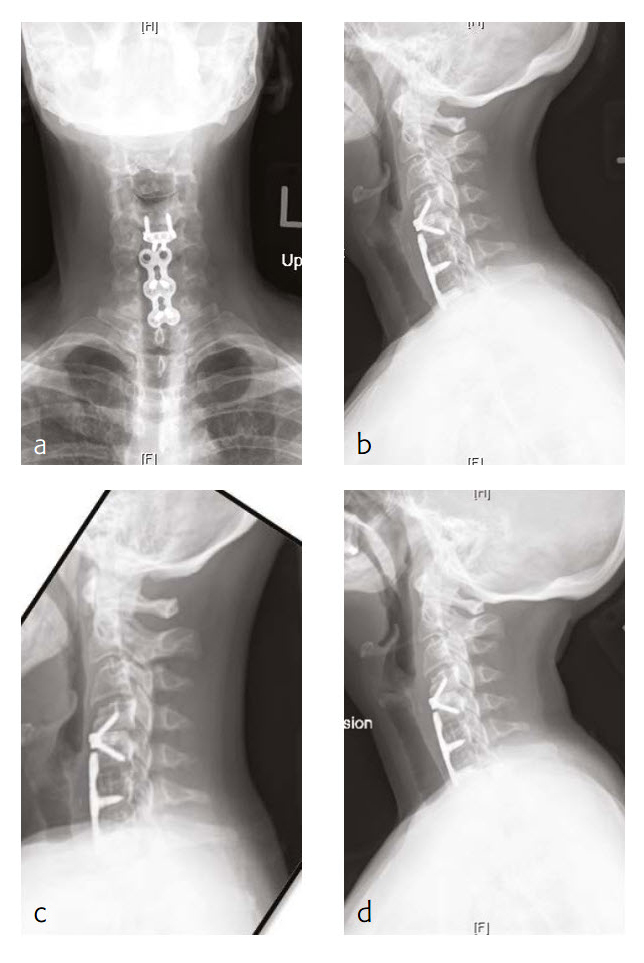

Case 2: Neck pain with cervicogenic headaches

The patient works at a grocery store as a produce stocker and has a history of C5 through C7 ACDF done in 2005 (Fig 3). Her symptoms were relieved at that time, but she had quite severe neck pain and bilateral radicular symptoms. She had chronic C6 radiculopathy since recovery from that procedure, however, was able to return to work. Unfortunately, over the last 34 months, she has had a recurrence of symptoms, with constant neck pain and occasional cervicogenic headaches.

She will occasionally get bilateral pain, a pins and needles-type sensation through a number of distributions, including C5 through her shoulders, less occasionally through a C7 or C6 distribution. Movement of her neck was becoming increasingly painful, particularly with flexion and lateral flexion to the right and left.

She has tried a number of conservative modalities including narcotic pain medications, rest, heat, ice, physical therapy-type exercises, activity avoidance, and oral steroids. She states that she has had a steroid injection. These were not helpful for her. Eventually, she got an MRI and was found to have adjacent level disease.

On manual muscle testing, the patient had 5/5 strength bilaterally with shoulder abduction, elbow extension and flexion, wrist extension and flexion, finger abduction and grip strength.

The patient has appropriate range of motion through her cervical spine with flexion and extension, and lateral flexion and rotation. She gets grimacing pain with extreme ends of flexion as well as bilateral rotation and lateral flexion. She has no tenderness to palpation of the spinous process or paraspinous musculature of her cervical spine. She has decreased sensation in bilateral C5 distributions.

Follow-up (6 months)

The patient is now about 6 months status post a C4-C5 discectomy and interbody fusion with removal of preexisting C5 screws (Fig 4). She was recovering well and has not been taking any narcotic pain medication. She takes acetaminophen.